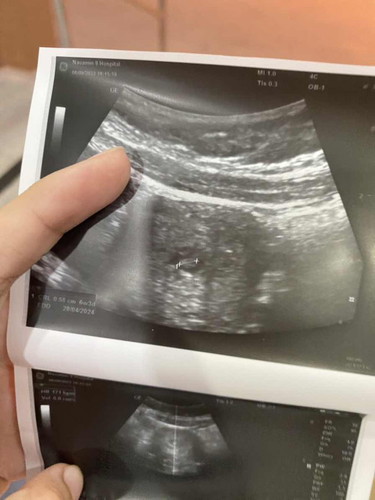

เมื่อวานมีเลือดออกค่ะแต่ไม่ปวดท้องไปหาหมอบอกแท้งคุกคามซาวเจอน้องได้ยินเสียงหัวใจปกติ6w3dได้ฉีดยา1เข็มวันนี้เลือดสีชมพูอ่อนๆถ้าไม่ใช่ทิชชูเช็ดก็ไม่ไหลค่ะนอนอยู่เฉยๆตลอดแบบนี้อันตรายมากมั้ยค่ะเลือดจะออกนานมั้ย ปล.อาทิตย์หน้าหมอนัดฝากครรภ์ค่ะ